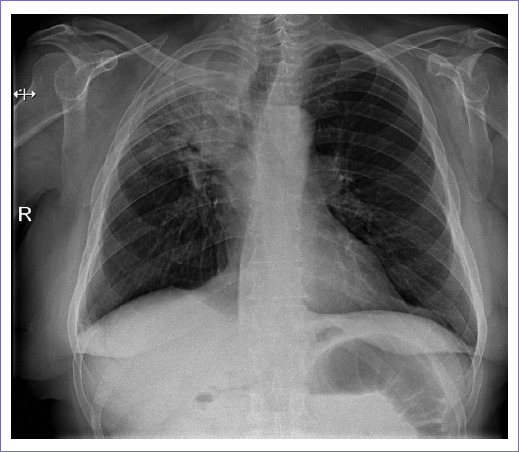

Acude al área de urgencias siete años después por hemoptisis de un mes de evolución, que inicialmente se trató en medio privado sin mejoría. Se refiere transfusión sanguínea de tres paquetes globulares con reporte de hemoglobina (Hb) externa de 8.9 postransfusión; se realizó broncoscopia en medio externo con reporte de tumor endobronquial de lóbulo superior derecho de 5 cm parahiliar y toma de biopsia con reporte histopatológico de carcinoma epidermoide, en nuestro Servicio de Urgencias con adecuada coloración mucotegumentaria y adecuado estado de hidratación, sin compromiso cardiorrespiratorio; se solicitó tomografía de tórax (Fig. 2). Laboratorios al ingreso: leucocitos 8.4, Hb 9.6, hematocrito (Hto) 29.4, recuento de plaquetas 361, creatinina 1.26, Fa 80, glucosa 99, potasio 4.0, sodio 140, tiempo de protrombina 11.8, tiempo parcial de tromboplastina 43.9 e índice internacional normalizado 1.07.

Cinco meses posteriores al inicio de gemcitabina se documenta por PET/CT y radiografía de tórax atelectasia del lóbulo superior derecho (Fig. 4), por lo que se decidió interconsulta a Neumología para posible colocación de stent bronquial y valorar inicio de radiocirugía.

Figura 4 Radiografía de tórax con hemitórax derecho con disminución en expansión secundario a opacidad parahiliar derecha con broncograma aéreo, condiciona retracción de la tráquea y mediastino.